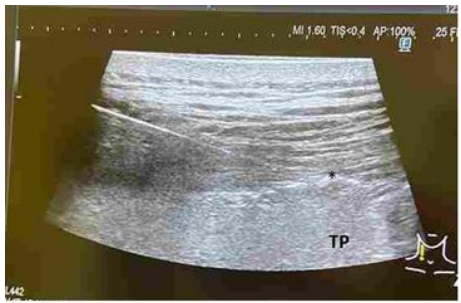

A 71 years old man with history of active Multiple myleoma was admitted with complaints of severe back pain on movements. He was unable to turn side ways and to get up from the bed. He was receiving chemotherapy for the same. Past history was significant for hypertension, Coronary artery disease on medical management, hypothyroidism. He was on Fentanyl transdermal patch 50 mcg every third day, Intravenous Morphine 3 mg SOS, Zolendronic acid, tablet Tramadol and paracetamol combination twice daily. On clinical examination, patient was having a pain score on NRS 8-9/10. On palpation, tenderness was elicited over the area corresponding to D8 level over the midline and right paraspinal region in the thoracic back. The pain was not radiating to bilateral upper limbs, anterior chest wall or lower limbs and no motor or sensory deficits were noticed. His MRI Spine revealed multiple wedge compression fractures at D5, D8, D10 levels (Fig1)

Fig- 1. MRI SPINE saggital section showing D8 vertebral fracture

However in comparison to the previous MRI, D8 fracture was relatively new but there was no underlying marrow oedema.